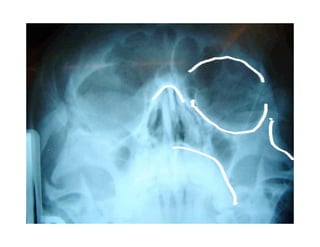

Este documento describe los principios de construcción de la arquitectura craneofacial, incluyendo el metamerismo, la simetría y la paquimería. Explica la organización peri-cavitaria del cráneo a través de columnas y vigas, y analiza las diferentes fascias profundas del cuello. También destaca la importancia de conocer la irrigación ósea con orientación quirúrgica, mencionando los principales aportes vasculares y suplementarios así como el origen, trayecto y retorno venoso de la carót